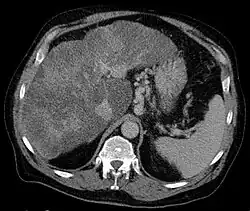

Axial CT showing varices of the fundus in liver cirrhosis with portal hypertension

Gastric varices can present in two major ways. First, patients with cirrhosis may be enrolled in screening gastroscopy programs to detect esophageal varices. These evaluations may detect gastric varices that are asymptomatic. When gastric varices are symptomatic, however, they usually present acutely and dramatically with upper gastrointestinal bleeding. The symptoms can include vomiting blood, melena (passing black, tarry stools); or passing maroon stools or frank blood in the stools. Many people with bleeding gastric varices present in shock due to the profound loss of blood.[1]